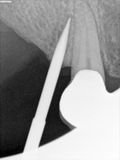

fredlibc | all galleries >> Galleries >> Mtiu - implant with bone expansion and graft > R1.jpg